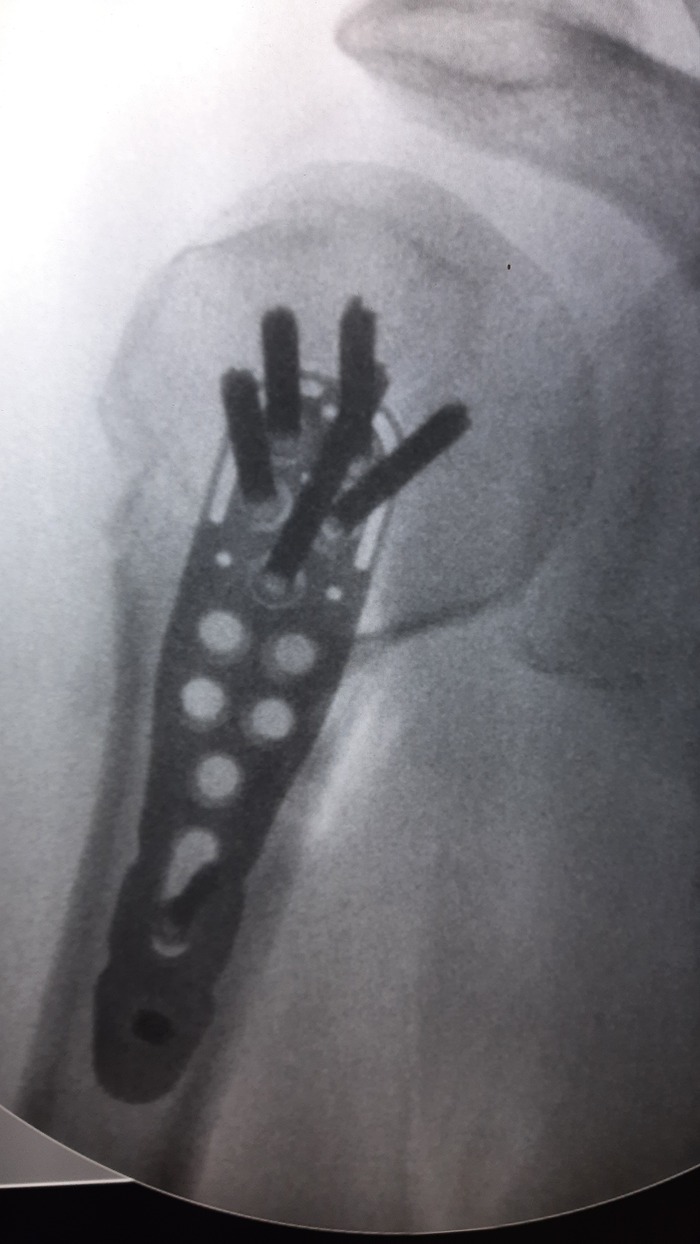

Ну и очень много рентгеновских снимков